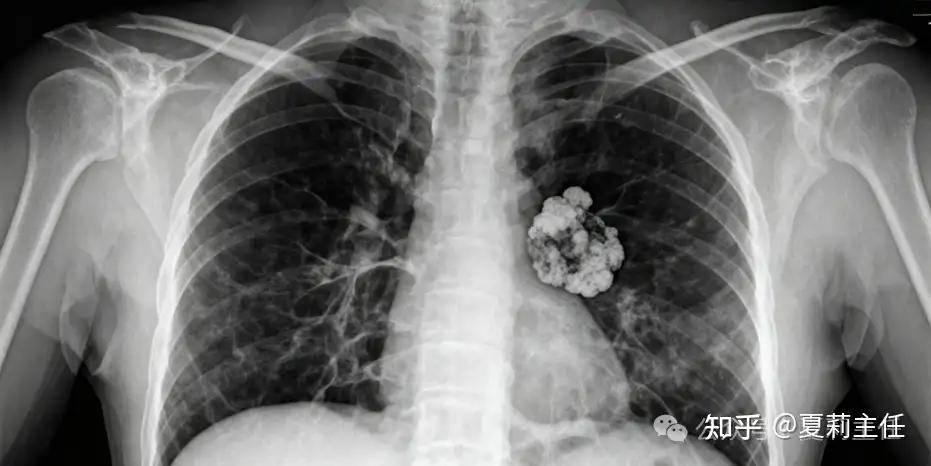

结合检查结果,夏主任轻拍陈阿姨肩膀,温和而坚定地告知她是肺腺癌ⅠB期,无基因突变,且没有脉管侵犯、肿瘤分化差等高危因素,适合微创手术,术后定期复查即可。弄清关键信息后,陈阿姨焦虑大减,很快配合安排手术。

这是所有问题的基础,也是医生制定治疗方案的核心依据。首先要明确病理类型,比如是肺腺癌、肺鳞癌还是小细胞肺癌?不同类型的肺癌,恶性程度和治疗敏感性不同 —— 肺腺癌可能有更多靶向治疗机会,小细胞肺癌则以放化疗为主;

再明确临床分期,分期越早治愈希望越大,比如Ⅰ期手术切除后效果较好,Ⅳ期多已出现远处转移,治疗重点是控制病情、延长生存期;还要问清是否存在EGFR、ALK等基因突变,这直接决定能否使用副作用相对较小的靶向药。